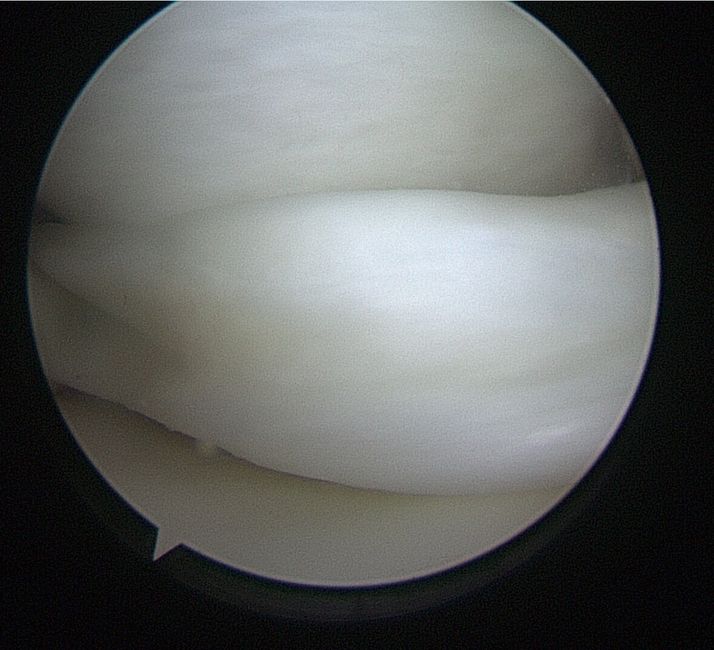

Bucket Handle Tear Blood Supply . Longitudinal tears that may take the shape of a bucket handle if displaced. This is because this area has rich blood supply and blood cells can. Tear caused by deterioration than one from an acute trauma that can occur earlier in life. Complete vertical tears can sometime twist within the joint known as “bucket handle” tears. There are six types of. These are unstable tears which. There are six types of meniscus tears: